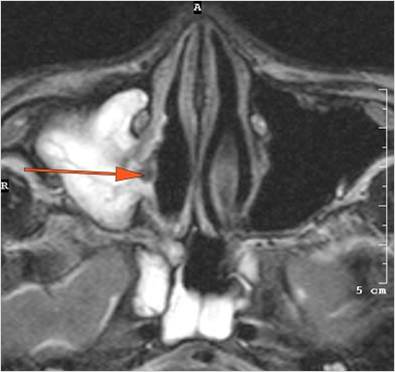

The superior and/or inferior ophthalmic veins are dilated or thrombosed. [Yes/No]

There is evidence of thrombus, thrombophlebitis or other occlusive or inflammatory process of the cavernous sinus. [Yes/No]